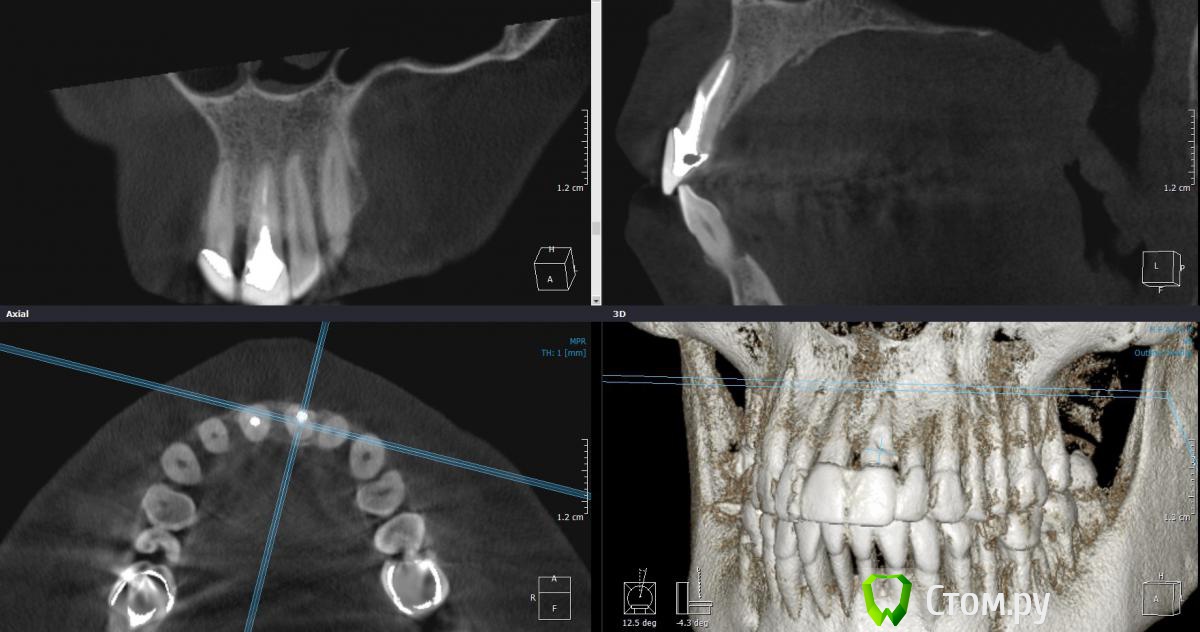

Dantist55 Опубликовано 14 апреля, 2014 Поделиться Опубликовано 14 апреля, 2014 Уважаемые коллеги, посоветуйте как быть в данной ситуации.21 подлежит удалению - перфорация передней стенки корня.Стоит ли одномоментно ставить имплант? Смущает отсутствие вестибулярной костной пластинки.У меня, к сожалению небольшой опыт одномоментной имплантации. Ссылка на комментарий

Alexey Doc Опубликовано 14 апреля, 2014 Поделиться Опубликовано 14 апреля, 2014 Одномоментно с удалением в вашем случае не получится.Необходима операция по увеличению объема костной ткани. Ссылка на комментарий

kriokov Опубликовано 14 апреля, 2014 Поделиться Опубликовано 14 апреля, 2014 помимо перфорации похоже нет и костного пика между 11 и 21 Ссылка на комментарий

ILGAMSA Опубликовано 14 апреля, 2014 Поделиться Опубликовано 14 апреля, 2014 А как бы сделали Вы?Соккет презервейшн.При наличии бугра с костью трепаном выпилил бы слизисто-костный блок и переместил бы в лунку.При отсутствии - метод рожка мороженого. В разделе уже был описан, поищите. 3 Ссылка на комментарий